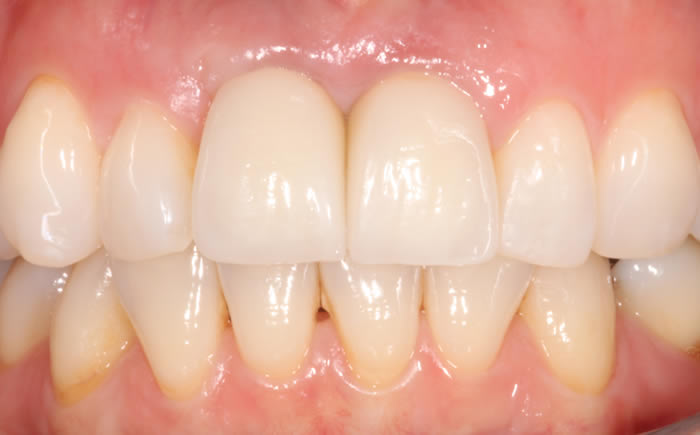

Before & After Gallery

More front teeth replaced by dental implants

Case Three (4 images)